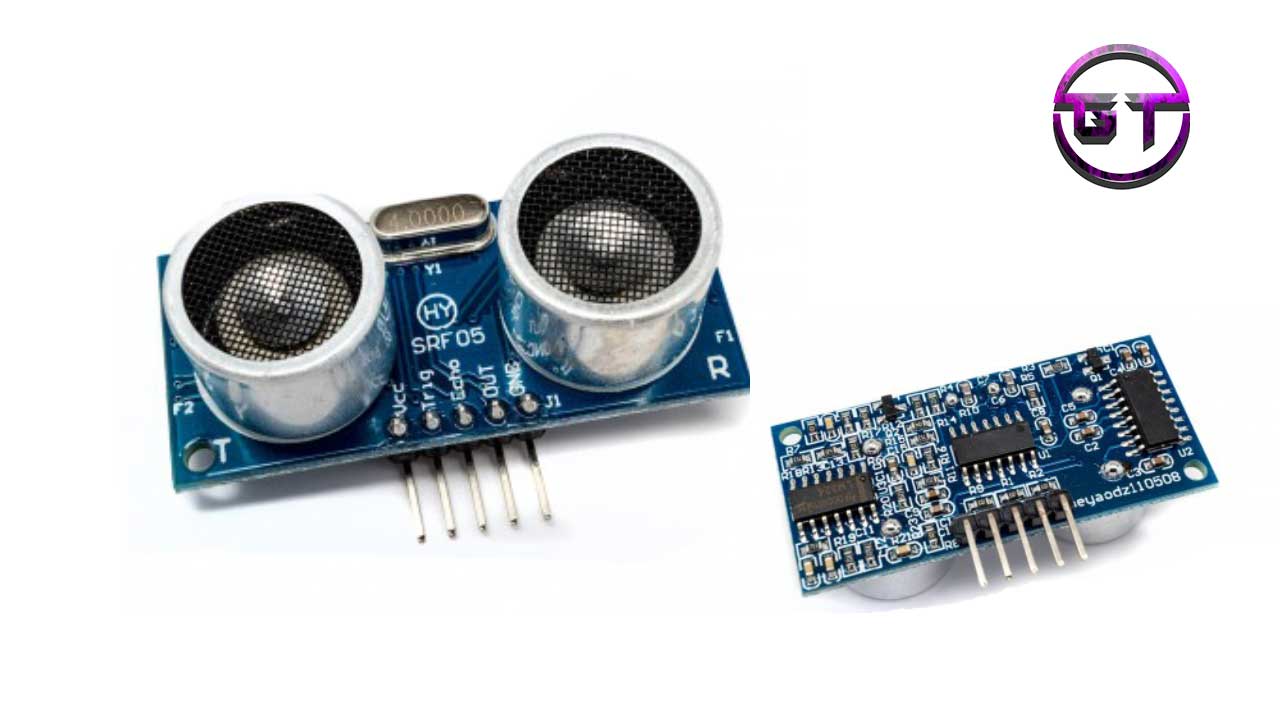

L’échographie est un examen médical, réalisé par un radiologue, qui repose sur l’utilisation d’une sonde émettant des ondes sonores à haute fréquence appelés ultra-sons, qui sont totalement sans impact sur l’organisme. Avant d’en bénéficier, les patientes se soumettent à une série d’examens comprenant en particulier un bilan hormonal et une . La Régie de l’assurance maladie du Québec (RAMQ) couvre les frais d’échographies qui sont prescrites par un médecin* et interprétées par un radiologue chez Imagix.Pourquoi faire une échographie pelvienne et des ovaires : grossesse, endométriose ? En permettant la visualisation des organes du pelvis, l’échographie pelvienne est .Critiques : 4

L'échographie est une technique d'imagerie médicale non invasive utilisée pour visualiser les organes et les tissus internes du corps.L'échographie du canal inguinal permet de recherche une hernie inguinale ou une cause de douleur du pli inguinal.

Afin de rechercher une infertilité chez la femme plusieurs examens sont effectués. Ce cours a pour objectif de vous montrer comment effectuer une échographie du canal inguinal : rappels anatomiques, technique d'examen, manoeuvres dynamiques et écho-anatomie normale. Un parenchyme ou stroma ovarien épaissit d’aspect hyperéchogène et hypervascularisé au Doppler, avec une disposition parfois contigüe des follicules, situés en périphérie des .Pourquoi faire une échographie pelvienne ? En effet, elle permet d’examiner l’abdomen de l’enfant sans utiliser de rayons X, ni injecter de produit de contraste, et c’est donc la modalité la plus utilisée. Trouver un spécialiste en Radiologie à proximité.Cela en fait une méthode d’imagerie idéale pour les populations sensibles, telles que les enfants et les femmes enceintes.